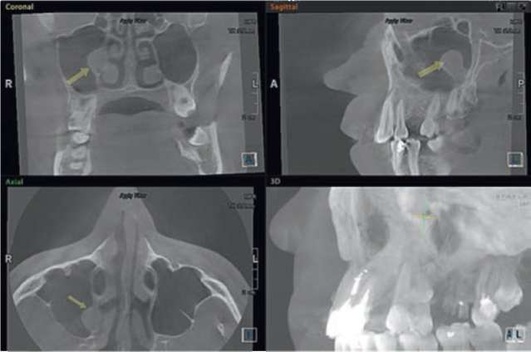

image

Рис. 5.89. Ретенционная киста правого верхнечелюстного синуса

Рис. 5.90. Новообразование медиальной стенки правой верхнечелюстной пазухи

Определенные трудности представляет дифференциальная диагностика одонтогенного синусита с опухолями верхней челюсти, особенно злокачественными на ранних стадиях, так как при злокачественной опухоли, исходящей из слизистой оболочки верхнечелюстной пазухи, как правило, развивается синусит. Однако при раке верхней челюсти наблюдают кровянистое отделяемое из носа или альвеолы удаленного зуба с характерным гнилостным запахом, часто деформацию верхней челюсти, нередко выбухание разрастаний через зубную альвеолу в полость рта или носа, подвижность зубов. При первых симптомах часто назначают противовоспалительное лечение, которое бывает неэффективным, что должно насторожить. В дальнейшем при раке усиливается деформация верхней челюсти, появляется экзофтальм, увеличиваются разрастания во рту и носовом ходе (рис. 5.91). На рентгенограмме при раке верхней челюсти отмечают резорбцию стенок верхнечелюстной пазухи, альвеолярного отростка верхней челюсти. Цитологическое и морфологическое исследования позволяют подтвердить диагноз.

Рис. 5.91. Злокачественное новообразование верхнечелюстной пазухи справа